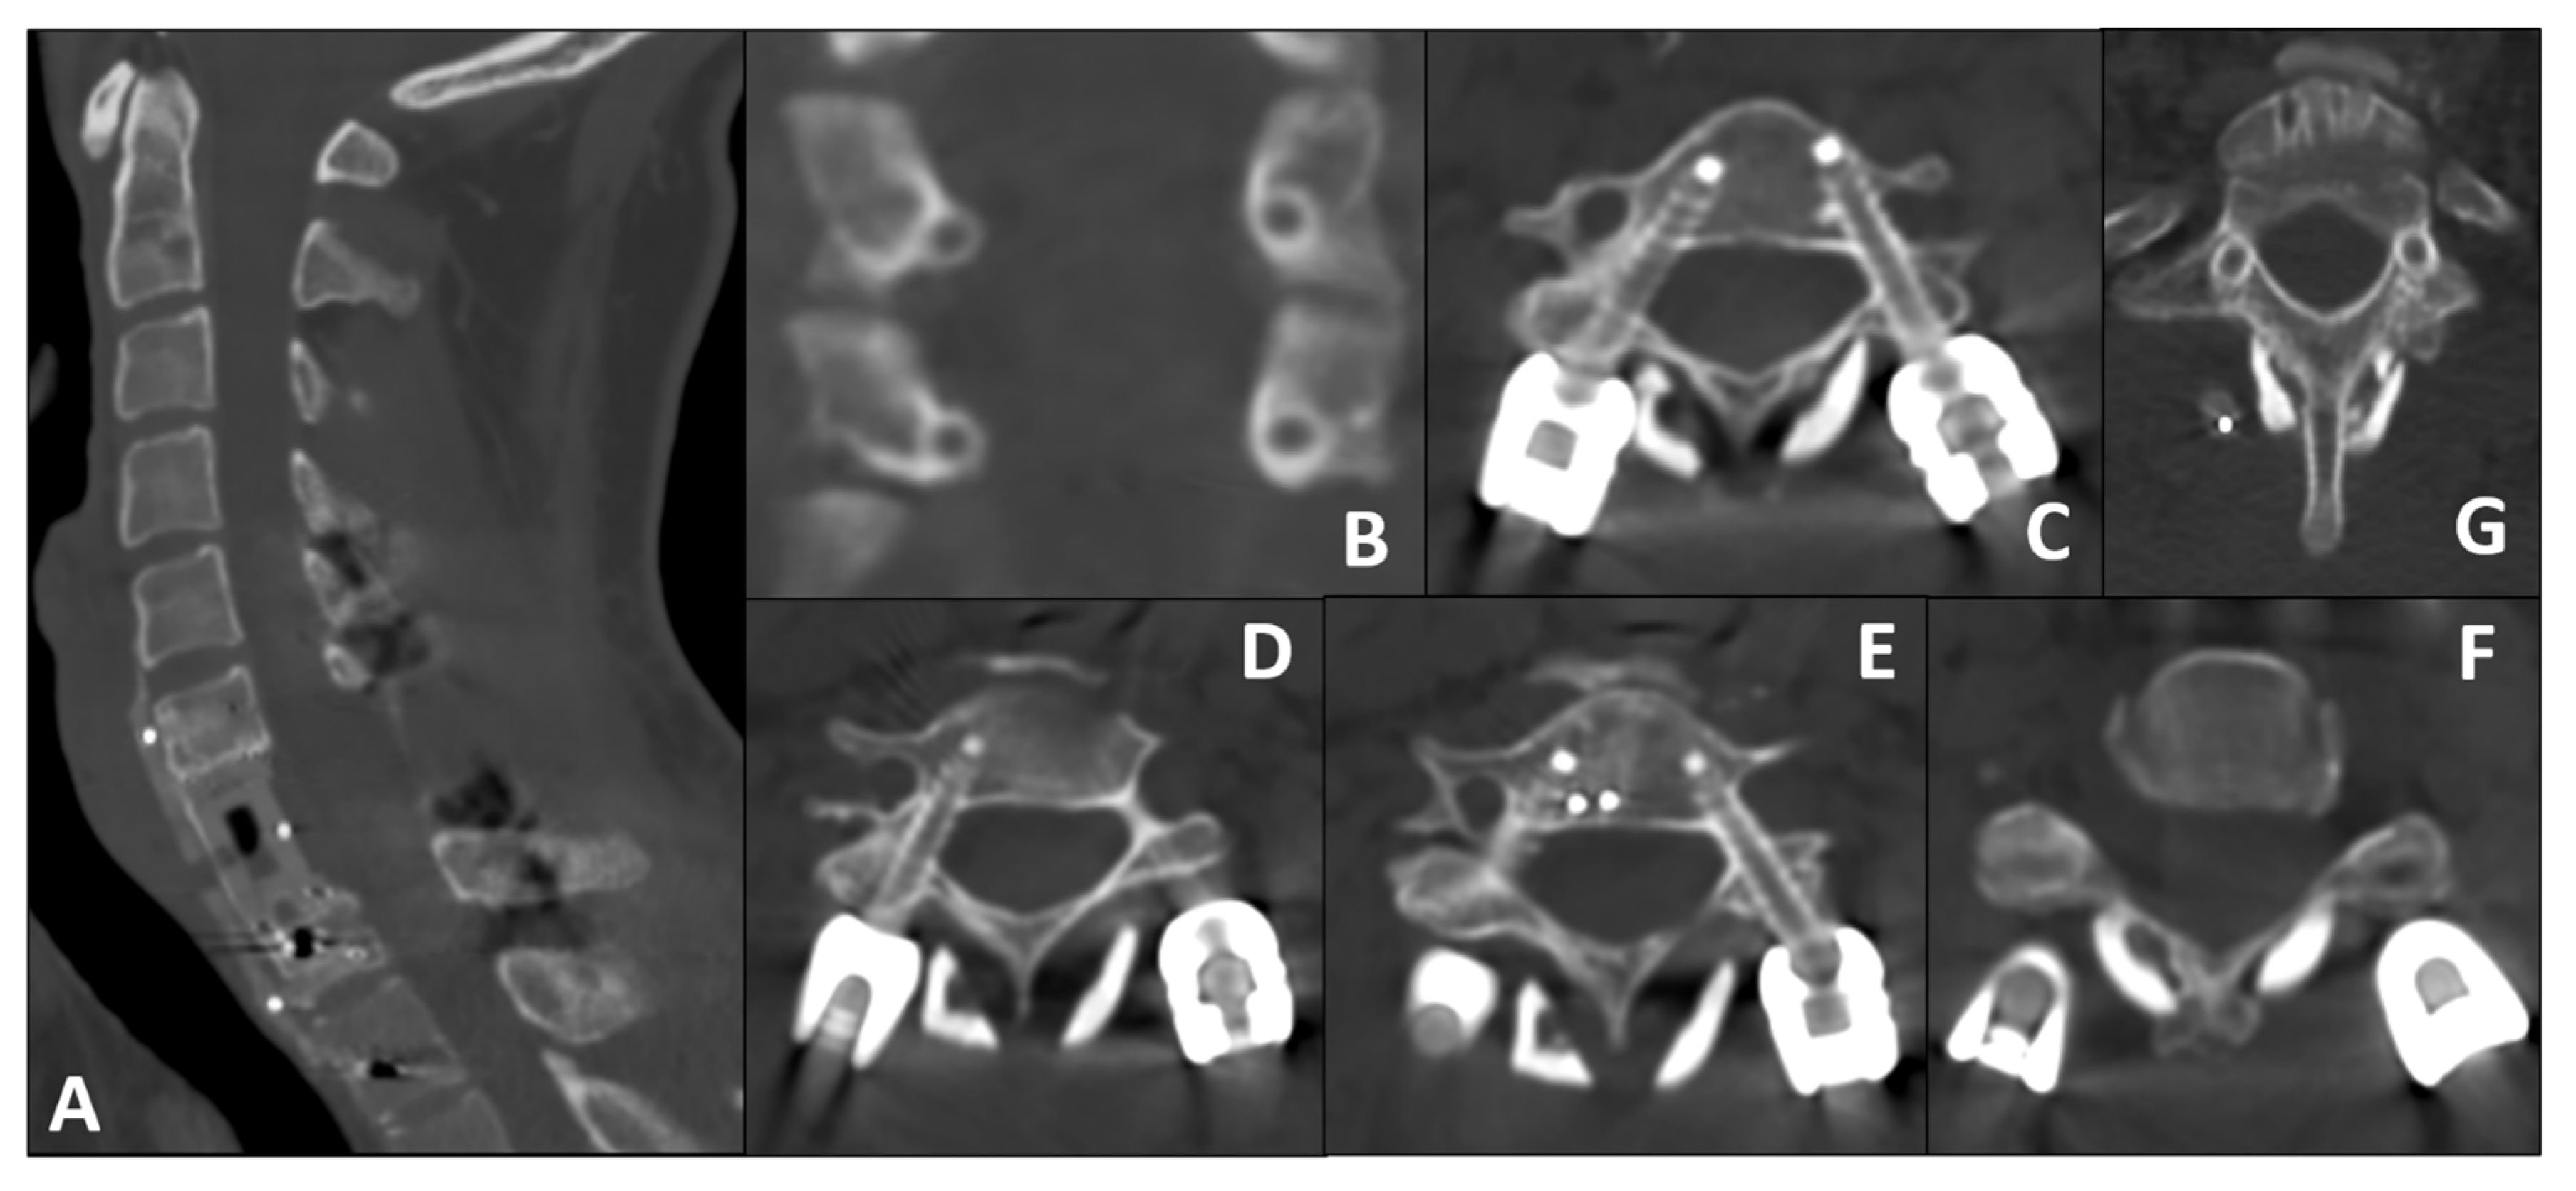

3.2. Posterior Step: Robot-Assisted Instrumentation

- Left Side (Repaired VA): The larger pedicle diameter allowed for a standard transpedicular trajectory.

- Right Side (Intact VA): Given the small pedicle diameter and the need to minimize lateral breach (risking injury to the only patent VA), we planned a small, controlled medial cortical violation, with limited encroachment into the canal, facilitated by robotic navigation. This choice is consistent with anatomical/clinical observations indicating higher vertebral artery risk with lateral breaches and short-term tolerance of limited medial violations [20,21,22].

| Level | Side | Intended Medial Encroachment | GR Grade | Revision Required |

|---|---|---|---|---|

| C5 | Right | Yes | C | No |

| C5 | Left | No | A | No |

| C6 | Right | Yes | C | No |

| C6 | Left | No | A | No |

| T1 | Right | No | A | No |

| T1 | Left | No | A | No |

| T2 | Right | No | A | No |

| T2 | Left | No | A | No |